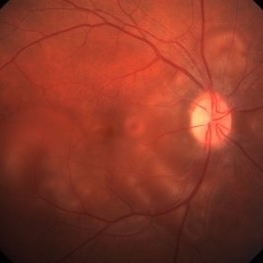

Preeclampsia in a 30-Year-Old - Color Fundus Photograph - RE

Nov 25 2015 by Roy Schwartz, MD

A 30-year-old presented with central scotoma and blurred vision a day following C-section for preeclampsia.

Photographer: Galit Yair Pur

Condition/keywords: blurred vision, central scotoma, preeclampsia